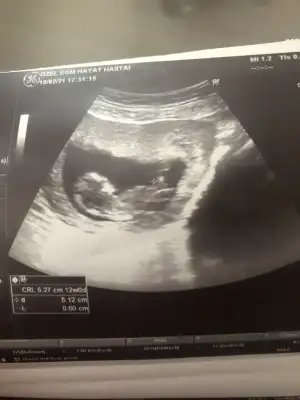

• Screenshot_20210207-165257_Gallery.webp

Screenshot_20210207-165257_Gallery.webp

15,8 KB · Görüntüleme: 50

Bakabilir ısın cok tesekkür ederim kız mı erkek ı Ay cok heyecanlı🧚‍♂️